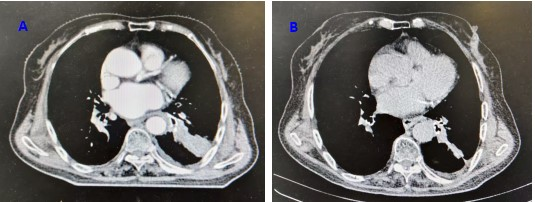

2025年8月25日复查胸部CT示:左肺门肿块及左下叶肺不张范围较前进一步缩小,纵隔淋巴结缩小。疗效评价维持PR,见图1。患者于2025年8月25日顺利出院,2周后继续开始特瑞普利单抗免疫维持治疗,并定期随访。

图1.放疗后图B肿瘤较放疗前图A肿瘤明显缩小